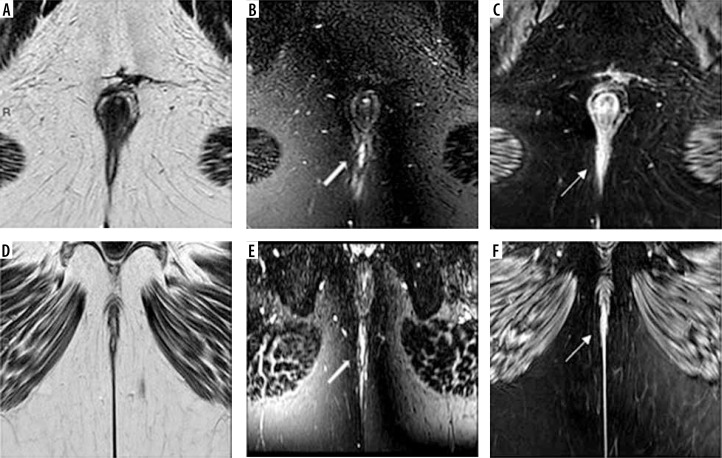

目的:肛瘘的诊断对外科医生来说是一个挑战。众所周知,磁共振成像(MRI)在其中起着重要作用。与二维(2D)序列相比,新的三维MRI序列VISTA(体积同位素涡轮自旋回波采集)可以改善肛周瘘的检测和表征。本研究的目的是通过对比增强(CE) 3D T1序列THRIVE (T1加权高分辨率各向同性体积检查)作为参考标准,比较新的3D MRI序列VISTA与广泛常规使用的T2 FSE脉冲序列在描述和表征肛周瘘方面的诊断性能。材料和方法:40名成年患者被纳入这项前瞻性研究。他们接受了常规T2 TSE和CE 3D T1 THRIVE序列的MRI肛周检查,并添加了新的3D MRI序列VISTA。T2、3D VISTA和(CE) 3D T1序列THRIVE影像分别由两名放射科医师评估,用于检测和表征肛周瘘,然后以(CE) 3D T1序列THRIVE作为参考,比较T2和3D VISTA序列。每个序列的敏感性、特异性和准确性由两名读取器计算。结果:阅读器1对3D VISTA的敏感性、特异性和准确性分别为92.5%、90.5%和93.6%,对T2 FSE的敏感性、特异性和准确性分别为84.1%、83.7%和87.3%。阅读器2对3D VISTA的敏感性、特异性和准确性分别为91.5%、92.8%和94.8%,对T2 FSE的敏感性、特异性和准确性分别为82.9%、84.5%和86.7%。结论:以CE 3D T1序列THRIVE为参照标准,与常规使用T2 FSE序列相比,肛周区3D VISTA脉冲序列在检测和表征肛周瘘方面具有更好的诊断性能。

Purpose: Diagnosis of perianal fistula represents a challenge for surgeons. It is well known that magnetic resonance imaging (MRI) plays an important role in that. The new 3D MRI sequence VISTA (Volume ISotopic Turbo spin echo Acquisition) can improve detection and characterization of perianal fistula compared with two-dimensional (2D) sequences. The aim of the study was to compare the diagnostic performance of the new 3D MRI sequence VISTA with the widely routinely used T2 FSE pulse sequence in depiction and characterization of perianal fistula by using the contrast-enhanced (CE) 3D T1 sequence THRIVE (T1-weighted high-resolution isotropic volume examination) as a reference standard.

Material and methods: Forty adult patients were enrolled in this prospective study. They underwent MRI perianal region examination using routine T2 TSE and CE 3D T1 sequence THRIVE with addition of the new 3D MRI sequence VISTA. T2, 3D VISTA and (CE) 3D T1 sequence THRIVE images were evaluated by two radiologists separately for detection and characterization of perianal fistula, then comparison between of T2 and 3D VISTA sequences was done using (CE) 3D T1 sequence THRIVE as a reference. Each sequence sensitivity, specificity and accuracy were calculated by both readers.

Conclusions: Using CE 3D T1 sequence THRIVE as the reference standard, 3D VISTA pulse sequence on the perianal region has better diagnostic performance in the detection and characterization of perianal fistula as compared to the routinely used T2 FSE sequence.